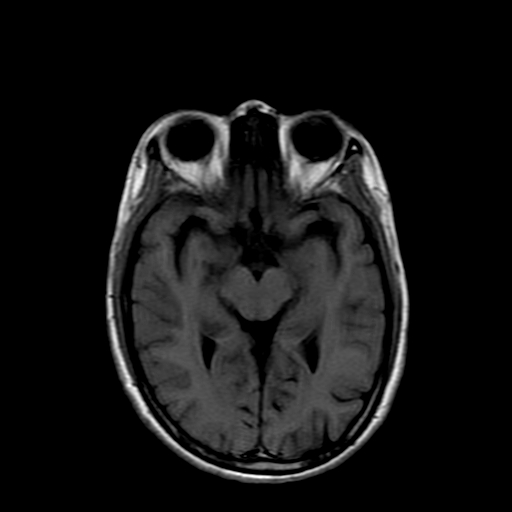

女性,47岁。mri号03027,外伤致头痛9天,抽搐一天,原无类似病史。

双侧海马的信号都有异常。

双侧海马硬化!

颞叶前部萎缩,海马萎缩,t2wi海马高信号,支持海马硬化。

双侧海马硬化.

双侧海马区t1低,t2高信号。为什么都考虑硬化?发病原因?鉴别诊断:炎症,梗塞等能一下子除外吗?